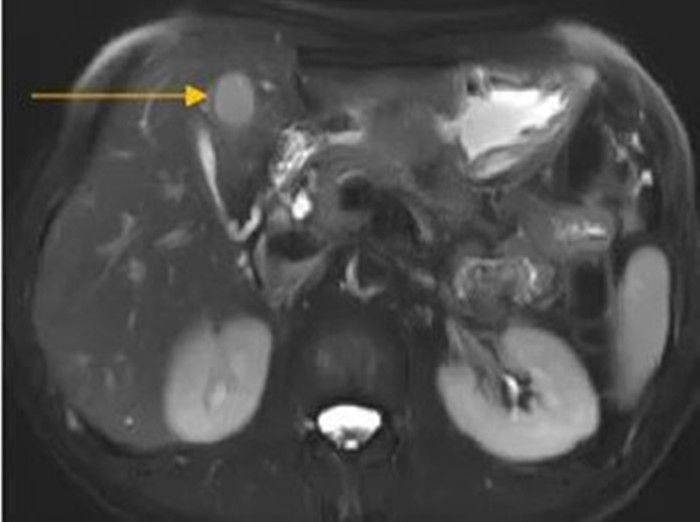

住院后經(jīng)胸腹部CT檢查,提示周先生胃部巨大腫塊穿破胃腔,可能累及到結(jié)腸,同時(shí)合并有胃旁淋巴結(jié)轉(zhuǎn)移、肝臟的轉(zhuǎn)移??吹竭@個(gè)檢查報(bào)告后,周先生和他的愛人一下子就泣不成聲了。

治療前肝臟的轉(zhuǎn)移灶